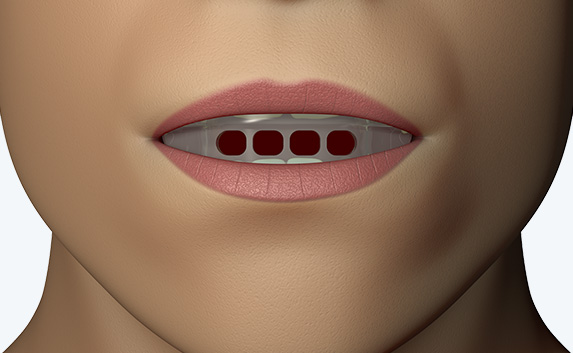

The Myosa®for TMJBDS®S1 is used in patients with a Breath Hold Time (BHT) of 20 seconds or more. It works by advancing the sleeper’s lower jaw and opening the bite, which has the effect of opening the airway. Additionally, the S1 has four breathing holes at the front to regulate breathing. For better retention during sleep, the patient can use the mouldable version of the S1 appliance (S1M). Progress to the S2 when the patient’s BHT reaches 35 seconds or more.